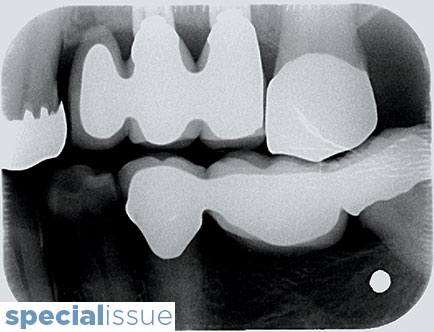

OHSP-Ross-main alternate text for this image